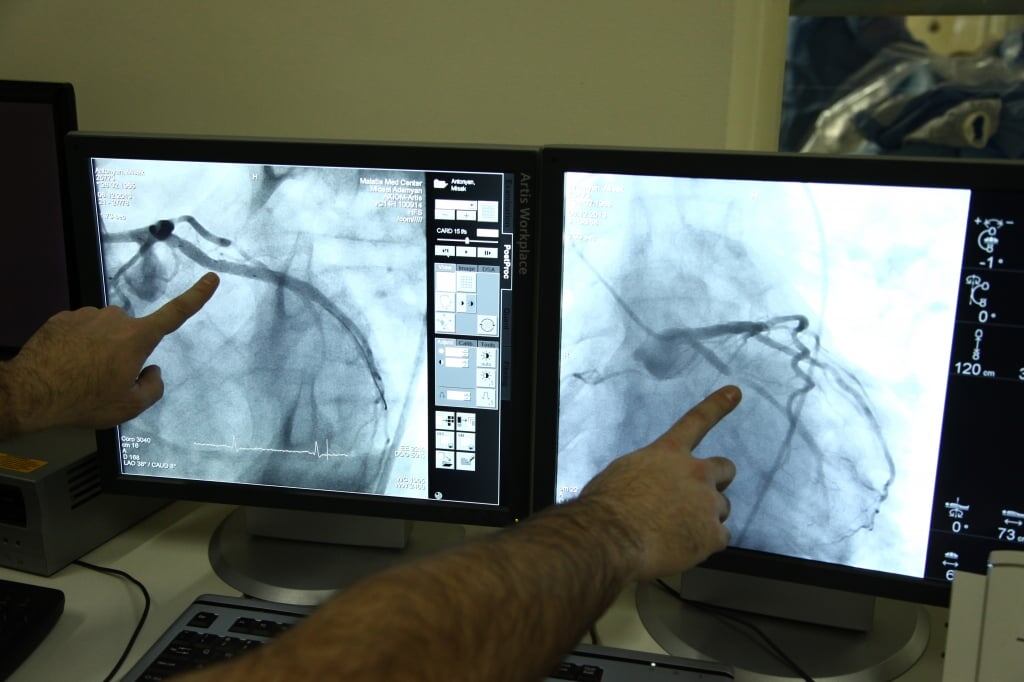

Давайте сразу договоримся: коронарография (КАГ) — это не полостная операция. Это малотравматичное диагностическое исследование сосудов сердца, которое чаще всего проводится через прокол в руке или паху. Оно нужно, чтобы за 15-20 минут узнать, есть ли в ваших сосудах те самые «пробки» (атеросклеротические бляшки), из-за которых сердцу не хватает кислорода для нормальной работы. Более подробно я писал об этом тут.